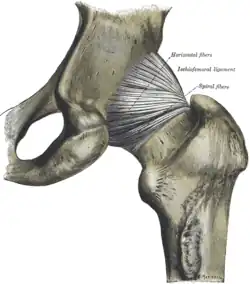

Bänder

Das Hüftgelenk ist mit dem kräftigsten Bandapparat des menschlichen Körpers versehen, da es aufgrund des umfangreichen Bewegungsspielraums auf eine knochenbetonte Roll-Gleitbewegung (Arthrokinematik und Osteokinematik), wie etwa beim Kniegelenk verzichtet.

Die kapselverstärkenden Bänder sind derart schraubenförmig um den Oberschenkelknochenhals gewickelt, dass sie im Stand und in Streckung (Extension) gespannt sind, während sie sich bei Beugung (Flexion) abwickeln. Von jedem der Teilknochen des Hüftgelenkes windet sich ein Band zum gelenknahen Oberschenkelknochen. Sie stabilisieren, indem sie für eine Kontakterhaltung zwischen Gelenkpfanne und -kopf sorgen. Außerdem besitzt die knöcherne Gelenkpfanne ein zusätzliches Band, wodurch sie vervollständigt wird. In den Oberschenkelknochen führt noch ein Band, welches den Hüftkopf versorgt.

Bänder außerhalb der Kapsel

- Das Ligamentum iliofemorale („Darmbeinschenkelband“) ist mit ca. 350 kg Zugfestigkeit das stärkste Band des Körpers. Es verläuft von der vorderen unteren Beckenspitze (Spina iliaca anterior inferior) und dem Rand des Pfannendachs bis zur Linie zwischen den beiden Oberschenkelrollhügeln. Man unterteilt es in einen stärkeren Zügel, der weiter oben und parallel zur Oberschenkelknochenhalsachse verläuft (Pars transversa) und einen schwächeren Zügel, der etwas weiter unten und parallel zur Oberschenkelknochenlängsachse verläuft (Pars descendens). Gemeinsam verhindern beide Zügel ein Nach-hinten-Kippen des Beckens und stabilisieren somit die Standbeinphase, also die Streckung. Der obere Zügel hemmt zusätzlich die Auswärtsdrehung (Außenrotation), der untere Zügel hemmt die Innenwärtsdrehung (Innenrotation).

- Das Ligamentum ischiofemorale („Sitzbeinschenkelband“) verläuft vom Sitzbein zum Ansatz des oberen Zügels des Darmbeinschenkelbandes. Es strahlt außerdem in das Ringband ein. Das Sitzbeinschenkelband hemmt die Innenwärtsdrehung.